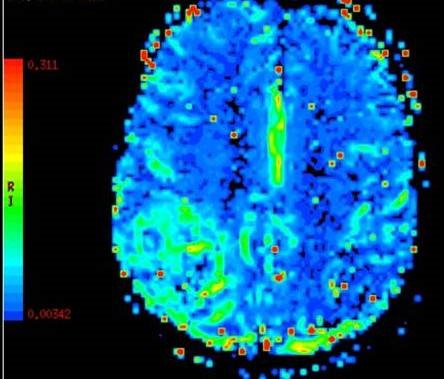

Arterial Spin Labeling MRI Perfusion image A for Radiology

How it works: Arterial Spin Labeling or ASL is a non-invasive method of measuring cerebral blood flow, or blood flow in the brain. The technique does not require intravenous contrast and can be performed on patients of all ages. The scanner creates an image showing relative changes in cerebral perfusion. Additional techniques can be performed that can show actual flow over time (Multiphase ASL). These techniques are most beneficial to patients with vascular stenosis, stroke, arteriovenous malformations, and tumors.

Equipment: Our MRI suite uses the latest Phillips 3.0 tesla magnet coupled with a state of the art Phillips Clinical ASL software package. Processing is performed automatically as soon as the scan is completed and images are available for immediate interpretation.

Arterial Spin Labeling MRI Perfusion image B for Radiology

Benefits: ASL is non-invasive so it can be performed on any routine brain MRI on any patient regardless of intravenous access, contrast allergy, or renal status. In young patients ASL is the optimal technique because the child’s veins can be too small to inject a rapid contrast bolus needed for other forms of MRI perfusion (DSC LINK). ASL can show perfusion abnormalities when all other MRI sequences appear normal. The best example of this is a patient with a transient ischemic attack or TIA. These patient’s have brief stroke like symptoms, but may have a normal MRI. ASL perfusion can reveal subtle perfusion changes that could allow possible therapeutic interventions to prevent a future stroke.

Exam Preparation: The technologist will interview you prior to scan to make sure you have no contraindications to being in the MRI scanner. Patients with braces or other metal near the head or neck may not be suitable for ASL because of the artifacts the metal can cause. Also individuals who have received MRI gadolinium based intravenous contrast within 48 hours of the ASL exam may not be suitable for perfusion imaging because of additional artifacts.

What to expect: ASL alone takes approximately 4-5 minutes of scanner time. The study is done in conjunction with routine anatomic imaging.

Content by Dr. Jeffrey Pollock